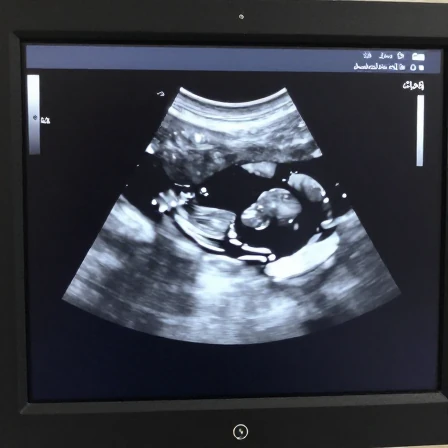

سونوگرافی جنسیت

سونوگرافی

1404/11/16

مقدمه: اشتیاق به دانستن جنسیت جنین سونوگرافی جنسیت یکی از هیجان انگیزترین مراحل دوران بارداری برای والدین است. ا...

آمادگی قبل از سونوگرافی

مقدمه: چرا آمادگی قبل از سونوگرافی اینقدر مهم است؟ وقت سونوگرافی گرفته اید و آماده اید تا با استفاده از تکنولوژی اولت...